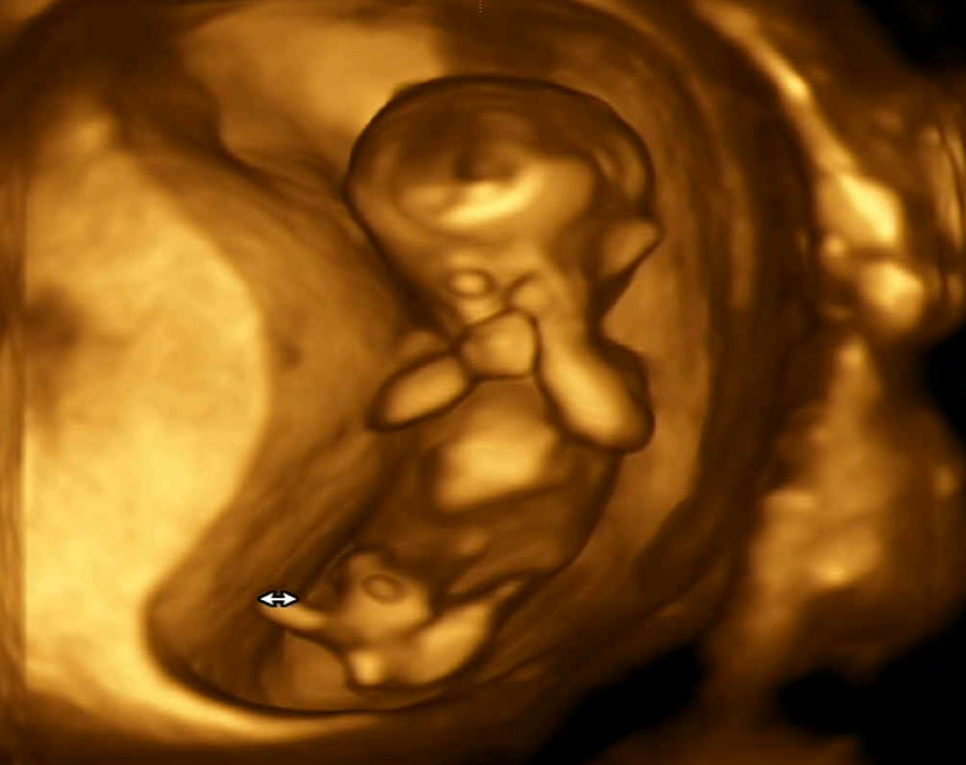

일단 1차 기형아 검사 초음파로 제일 먼저 확인했던 머리~미골 길이 ㅎㅎ #임신 12주차 정도가 되면 6~7cm 정도가 된대요. ^^

그다음에 본 뇌!#임신기 형 검사에서 뇌 초음파는 처음 봤는데 뇌가 나비 모양이었어요? 다 알고 있었어요?되게 신기했어요뇌가 나비 모양으로 성장을 했는지 머리의 가로 길이를 쟀습니다.가로 길이는 2센치 정도 나왔네요. ~

그리고 그 유명한 #나무투명 대검사! 나무투명대가 너무 두꺼우면 다운증후군과 에드워드 증후군이 있을 확률이 높대요. ㅠㅠ나무의 투명대는 3mm를 넘지 않으면 안된다고 합니다만, 오토는 1.7mm로 통과했습니다. 후우~

안녕하세요~해주는오토,그리고콧날이잘자라있는지확인하는데,이것도다운증후군과관련이있대요.다행히 코뼈도 멋있네요손가락도 5개예요. 이제 뼈가 생겼거든요.손으로 안녕이라고 인사하는 것 같다고 남편이랑 설렌다..ㅋㅋㅋㅋㅋㅋㅋㅋㅋㅋㅋㅋㅋㅋㅋㅋㅋㅋㅋㅋㅋㅋㅋㅋㅋㅋ

심장 박동도 확인해주시고요153비트가 나왔는데 정상이라고 하더라고요